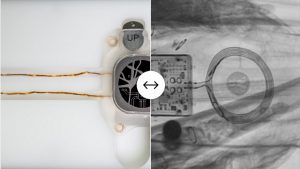

Pentru a-și ajuta pacienta să meargă din nou, cercetătorii au instalat implantul direct în măduva spinării pentru a reactiva neuronii care reglează presiunea sangvină şi a evita astfel starea de leşin.

Implantul utilizat constă într-o serie de electrozi conectaţi la un generator de impulsuri electrice, folosit în mod obişnuit pentru tratarea durerilor cornice. El a ameliorat capacitatea organismului de a regla presiunea arterială şi a permis pacientei să se poată menţine în poziţie verticală fără să ameţească şi să poată face fizioterapie pentru a putea merge din nou.